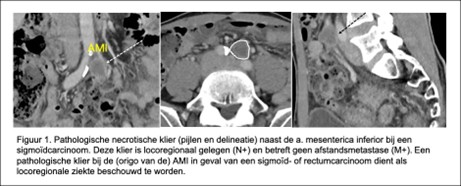

Een belangrijke valkuil bij sigmoïdtumoren (evenals bij rectumcarcinoom) is om klieren rond de origo van de arteria mesenterica inferior foutief te interpreteren als para-aortaal gelegen (met als consequentie het foutief stadieren van M1-ziekte). Het is daarom belangrijk om goed te beoordelen wat de locatie is van dergelijke klieren en klieren bij de origo van de AMI als locoregionaal te beschouwen (zie Figuur 1), (Storm, 2019).

De review van Curvo-Semedo (2019) toont dat de diagnostische accuraatheid van MRI voor detectie van pathologische lymfeklieren (cN+) ongeveer 60 tot 82% bedraagt. Een studie van deze review toonde een sensitiviteit en specificiteit van 47 tot 68% en 64 tot 86 %. Criteria voor pathologische klieren varieerden tussen deze studies: korte as ≥ 8mm, en/of cluster van 3 of meer klieren met diameter van > 5 mm, anderen gebruikten 10 mm of irregulaire begrenzing of heterogeen signaal. Geen enkele van deze studies maakte onderscheid in de locatie van de klieren (D1-D3) (Figuur 1).

Figuur 1. Classificatie van lymfeklierstations van het colon (Storm NTVO, 2019)

D1 betreft klieren lokaal vlak bij de tumor. D3 klieren liggen centraal langs de oorsprong van de vaatwortels (arteria mesenterica superior en inferior). D2 lymfeklieren liggen mesenteriaal dus tussen D1 en D3 in. D4 zijn para-aortale klieren en deze worden geclassificeerd als afstandsmetastasen (M1 ziekte). D3 voor linkszijdige tumoren zijn lymfeklieren centraal langs de origo van de a. mesenterica inferior/of a. colica sinistra. Voor rechtszijdige tumoren zijn dit lymfeklieren langs de a. en v. mesenterica superior. Let op: pathologische klieren van het sigmoïd die bij de inmonding van de arteria mesenterica inferior zijn gelegen moeten nog wel locoregionaal worden beschouwd en niet als para-aortale klieren worden benoemd (dus geen M1 ziekte)